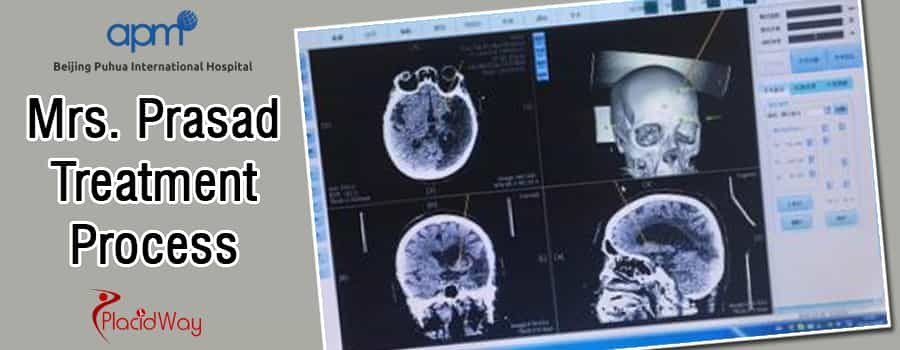

Процесс лечения

Операция прошла гладко, и пациентка хорошо поправилась. Послеоперационная КТ не выявила чрезмерного кровотечения, а целевая область была обработана точно.

Сразу после процедуры пациенту был назначен специализированный протокол внутривенного лечения с использованием питательных веществ для ускорения и усиления эффекта терапии стволовыми клетками, и уже в течение 1 недели были отмечены заметные изменения.

До операции : мышечный тонус был повышен в правой конечности (3/5), затруднение при ходьбе со слабой мышечной силой. Мышечная сила была 0-3/5 в правой верхней конечности (ближний конец 3/5, дистальный конец 0/5); правая нижняя конечность была 4/5.

После операции : мышечный тонус улучшился в правой конечности (1-2/5), улучшилась способность ходить. Мышечная сила составила 1-4/5 в правой верхней конечности (ближний конец 4/5, дистальный конец 1/5).